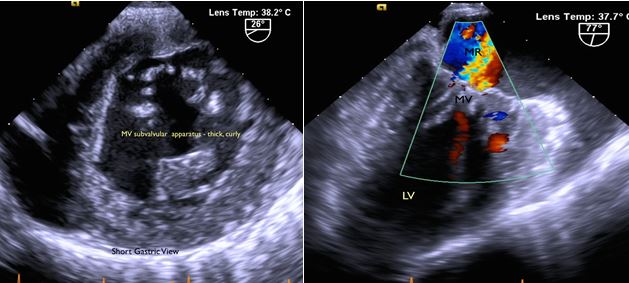

The patient's resting room air Sp02 was 94%. Her pulmonary function test showed a mixed obstructive and restrictive pattern with severely impaired diffusion capacity (Fig. 2). She had a BP 116/82, HR 80 NRRR, RR 22 non-labored, height of 154 cm, weight of 74 kg, and BMI 31.1. Her lungs were clear. She had a 3-4/6 systolic murmur over the left parasternal border with occasional radiation to the axilla and no diastolic murmur. An echocardiogram (Fig. 3) showed a left ventricular EF of 65%, mild concentric LVH, moderate MR, severe AS, mild AI, and mild pulmonary hypertension. A right heart catheterization showed RAP 6, PAP 38/2, PCWP 18, LVEDP 10, AV gradient 30, and AVA 0.7 cm2. Her coronary arteries were free of significant angiographic stenotic or occlusive disease.

Fig. 3A: Mitral valve leaflet: thickened, redundant. Moderate central regurgitation. Subvalvular apparatus: nodular, thickened, fused.

Fig. 3B: Aortic Valve: thickened, nodular, calcified valve. Severe AS and mild AI.